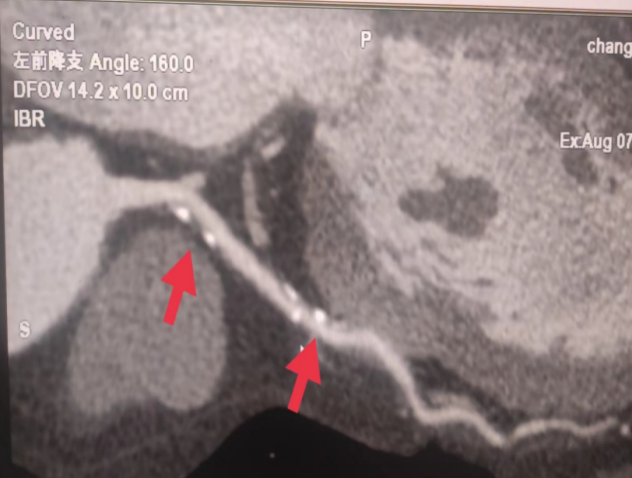

01**女士,70岁

2023年8月6日在邯郸仁泰东区体检冠脉CTA检查提示:左冠前降支近段钙化斑块,局部管腔轻微狭窄;中段混合斑块,局部管腔达重度狭窄(约90%左右);回旋支起始段钙化斑块,局部管腔轻度狭窄;右冠多发钙化斑块,近段轻微狭窄,中段轻度狭窄。首次回访2023年8月8日,通知客户去三甲医院进一步检查和治疗。2023年9月9日跟踪回访,客户家属反馈,已在邯郸某三甲医院完成支架手术,现服药治疗。